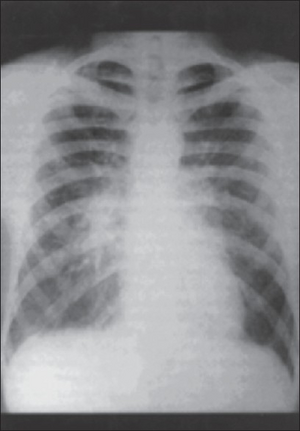

Atypical pneumonia- X-Ray chest showing right peribronchial central infiltrate

Chest radiographs (X-ray photographs) often show a pulmonary infection before physical signs of atypical pneumonia are observable at all.[5] This is occult pneumonia. In general, occult pneumonia is rather often present in patients with pneumonia and can also be caused by Streptococcus pneumoniae, as the decrease of occult pneumonia after vaccination of children with a pneumococcal vaccine suggests.[16][17]

Infiltration commonly begins in the perihilar region (where the bronchus begins) and spreads in a wedge- or fan-shaped fashion toward the periphery of the lung field. The process most often involves the lower lobe, but may affect any lobe or combination of lobes.[5]